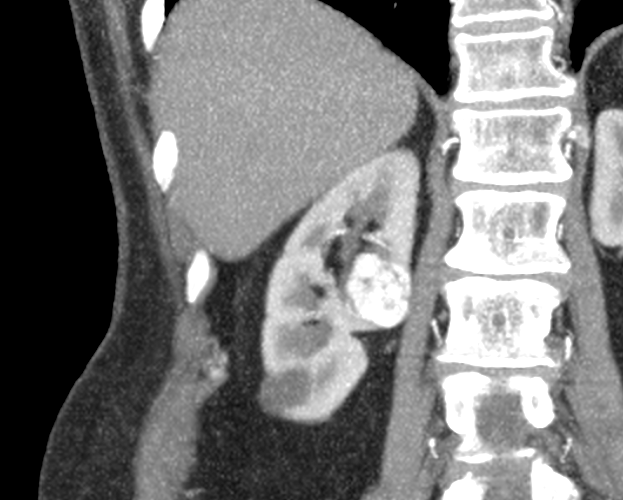

Una paciente de 74 años presenta un tumor de 22x25mm en su riñón derecho que fue hallado por un estudio de tomografía.

Luego de unos meses, la paciente vuelve al consultorio para realizar seguimiento, donde el doctor decide realizar una ecografía de control. En la misma, se reconfirma el diagnóstico de tumor renal hiliar en valva posterior del riñón derecho. Con este resultado, se decide realizar una intervención quirúrgica. Para la misma, dadas las características de la masa anómala, el Dr. Jurado solicita un modelo 3D para planificar la cirugía.